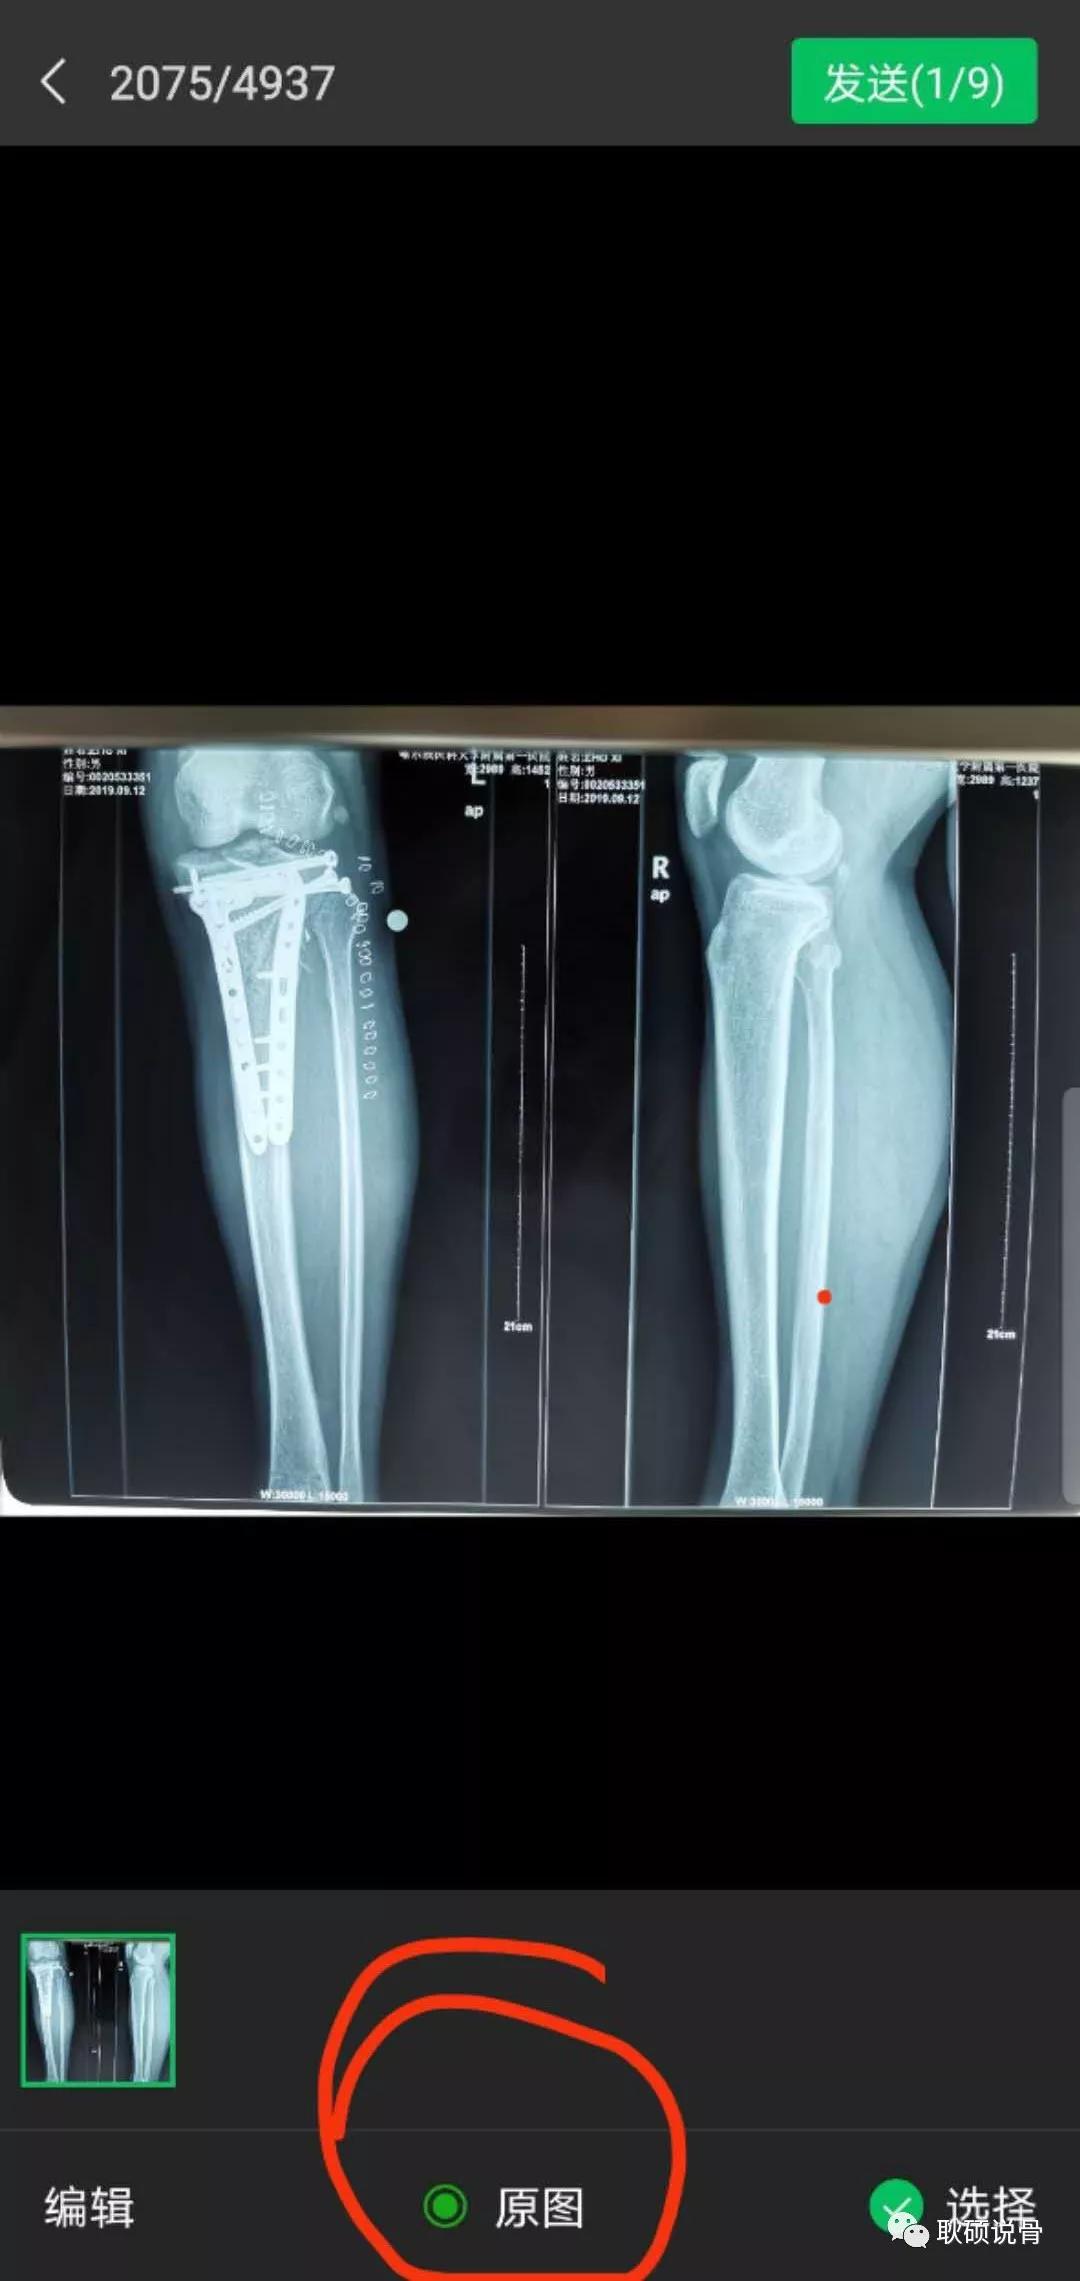

4、用手机相机拍照后,一定要点击最下方的“原图”发送: